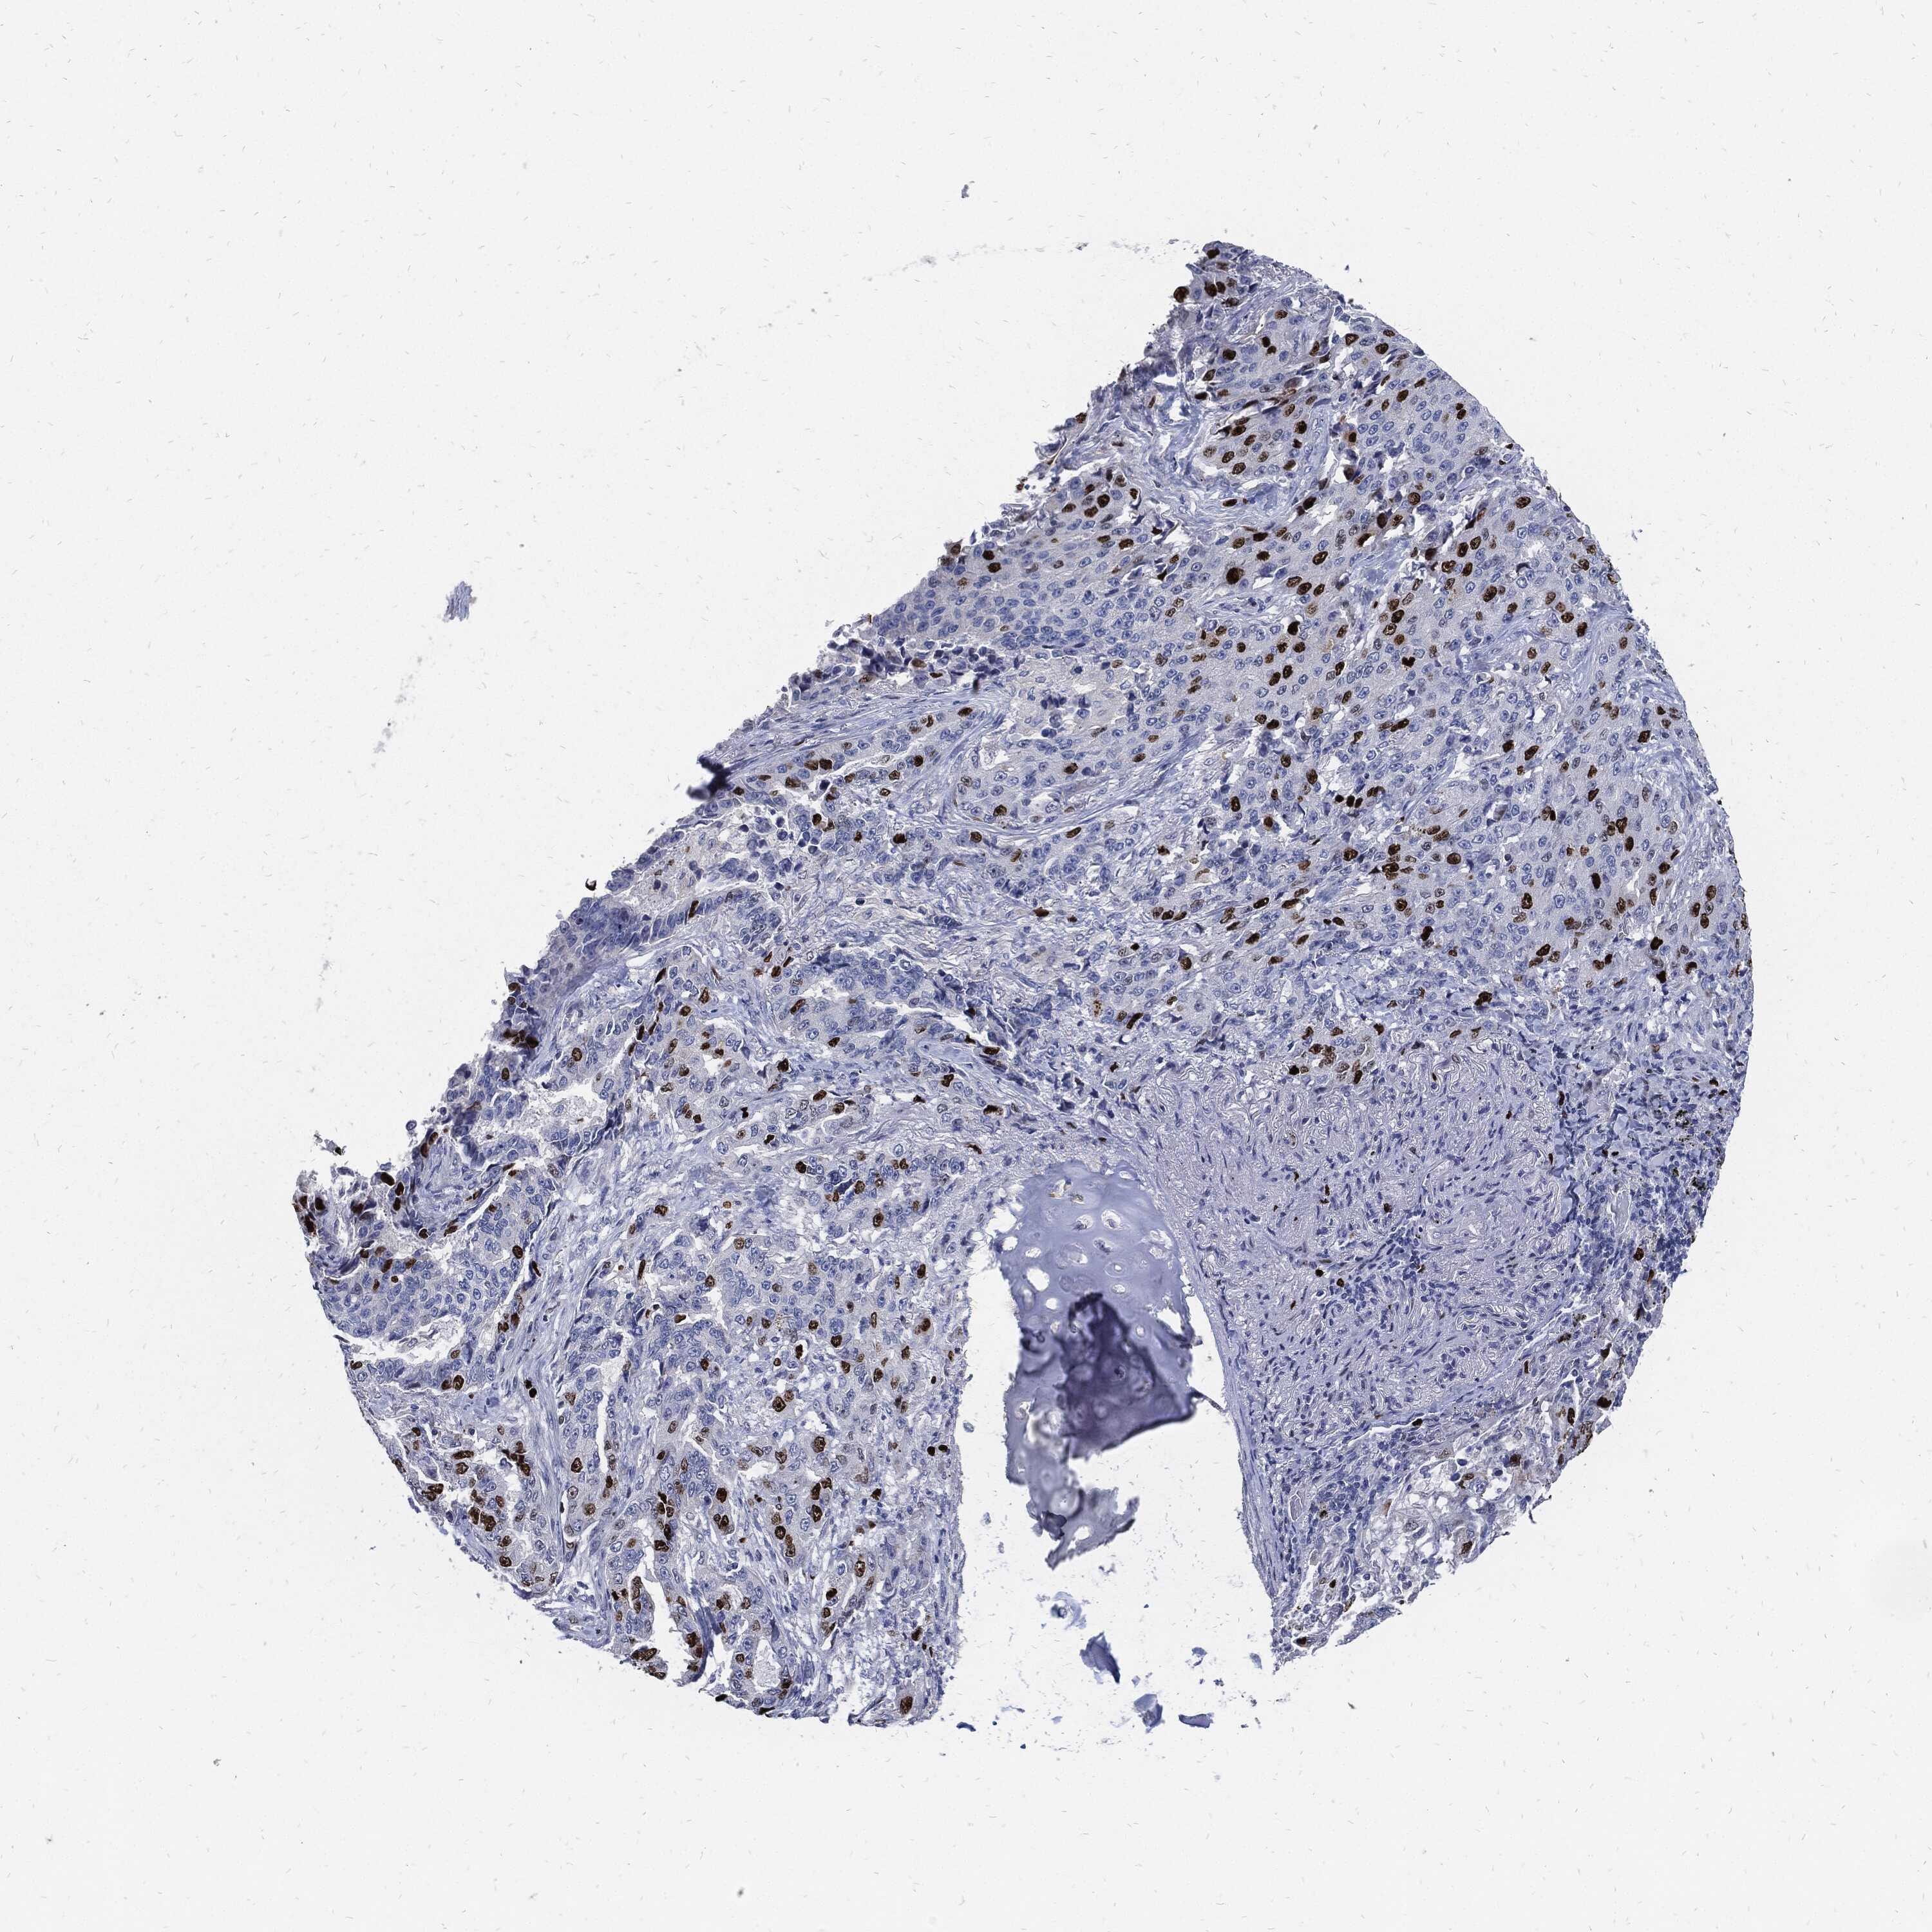

CANCER LUNG CANCER Show tissue menu

LUAD TCGA LUAD VALIDATION LUSC TCGA LUSC VALIDATION PROTEIN LUAD CPTAC PROTEIN LUSC CPTAC PROTEIN EXPRESSION

ANTIBODIES

AND

VALIDATION

MKI67 is validated prognostic, high expression is unfavorable in Lung Adenocarcinoma (validation)